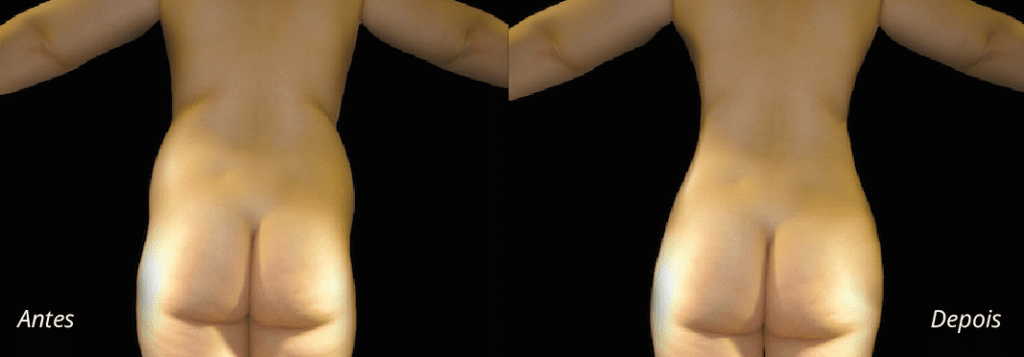

Imagens antes e depois